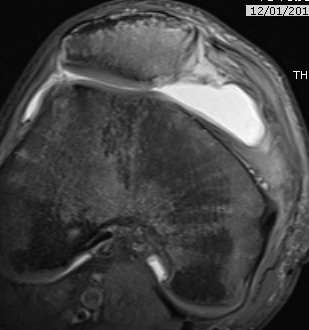

MRI

Demonstrates

- MPFL tear

- cartilage damage

- loose body

Osteochondral fracture (40-50%)

- LFC or medial facet patella

- patient will have haemarthrosis